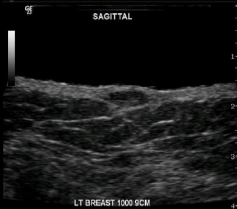

Identify this image.

Acute mastitis